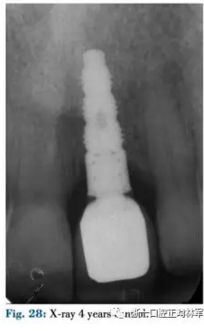

4月后在個(gè)性化基臺(tái)上粘臨時(shí)牙促進(jìn)組織成熟,8月后修整,最后用全瓷冠修復(fù)(圖26-29)。